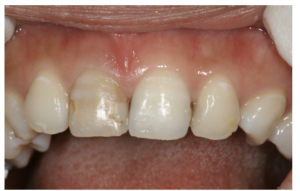

本報告はヘルシンンキ宣言を順守し, 行った. 初診から治療終了時までの顔面写真, 口腔 内写真, エックス線写真等の資料, ならびに各種診察結果, 分析結果, 診断結果, 治療方針, 治療経過等を記した書類を本症例報告に使用することを患者本人に説明し, 論文に掲載す る承諾を得た. 患者:24 歳3 カ月, 女性. 主訴:1 本だけ色の異なる歯があるので, 白くしたい. 既往歴:局所麻酔の異常なし, 全身疾患, 服薬などの, その他の特記事項なし. 現病歴:11 歯は約7 年前に, 一過性の冷水痛を覚え他院を受診した. 齲蝕症との診断によ り, コンポジットレジン修復を受けた. その後問題なく経過していたが, 約4 年前 に自発痛が生じ, その後, 次第に色が変わり気になってきたという. 現症:11 歯は歯冠全体が一様に変色し, 近遠心に3 級コンポジットレジン修復が施されて いたが, 修復物辺縁に褐線が認められた(図1). VITA classical シェードガイド (VITA)による視感比色法ではA3 よりも彩度が高かった(図2). 嗜好品としては, 喫 煙はないがコーヒーを1 日当たり2~3 杯程度飲んでいるという. エックス線検査で は根管充填状態は良好で, 根尖部の異常は認められなかった(図3).

図1 初診時の口腔内写真

24 歳 女性